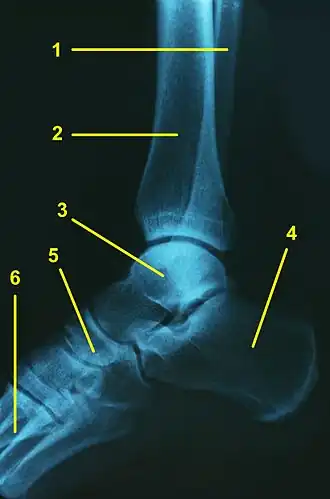

L'articulation talo-crurale (ou articulation tibio-astragalienne ou articulation tibio-tarsienne ou articulation du cou-de-pied ou articulation de la cheville) est l'articulation trochléenne qui unit le pied à la jambe au niveau de la cheville.

L'articulation talo-crurale est formée par les extrémités distales du tibia et de la fibula formant un ensemble tenon - mortaise avec le talus. Les deux os de la jambe forment ensemble une mortaise qui enserre le tenon formé par le talus.

L'articulation talo-crurale met en jeu :

- la facette articulaire de la malléole médiale,

- la surface articulaire inférieure du tibia,

- la facette articulaire de la malléole latérale.

Ces trois facettes formant la pince de la mortaise.

La surface articulaire au niveau du tenon étant formée par la trochlée du talus.

Trochlée du talus

La trochlée du talus est constituée par les trois quarts postérieurs de la face supérieur du talus.

Elle présente une face supérieure en forme de poulie quadrilatère plus large en avant qu'en arrière et convexe dans le sens antéro-postérieur. Dans le sens transversal, elle est légèrement concave avec un sillon oblique en avant et en dehors pour répondre à la surface articulaire inférieure du tibia. Le bord latéral est plus et large que le bord médial.

Latéralement, la trochlée se prolonge par la facette malléolaire latérale du talus qui répond à la facette articulaire de la malléole latérale. Cette surface est triangulaire à base supérieure, à concavité prononcée de haut en bas et très légèrement convexe, voire plane, dans le sens antéro-postérieur.

Médialement, la trochlée se prolonge par la facette malléolaire médiale du talus qui répond à la facette articulaire de la malléole médiale. Cette surface est en forme de virgule concave en bas et de pointe antérieure. La surface est plane.